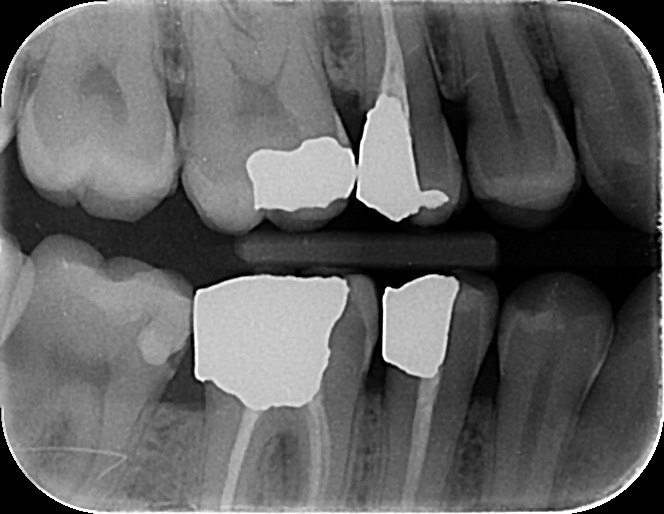

5. Which surface needs restoration?

6: What is the caries level of mesial of the tooth # 3.6?

7: What is the caries level of Distal of the tooth # 3.6?

8. Which surface needs restoration?